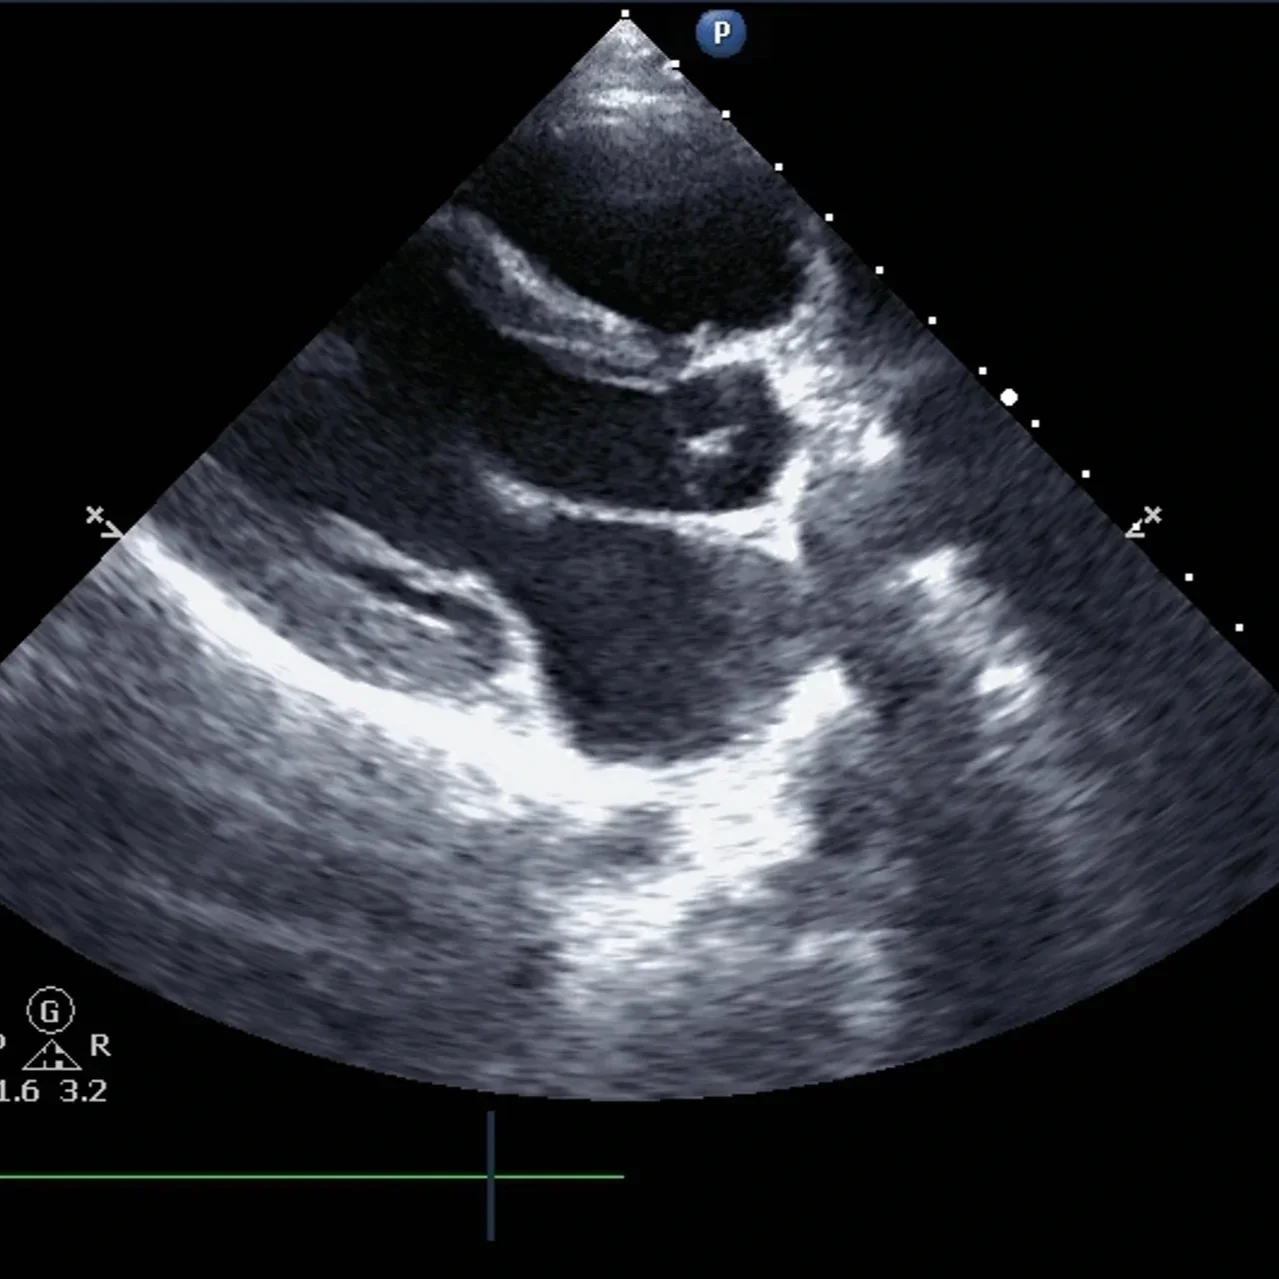

Interpreting what an echocardiogram can reveal about heart health highlights its importance in preventive care and ongoing cardiac management.